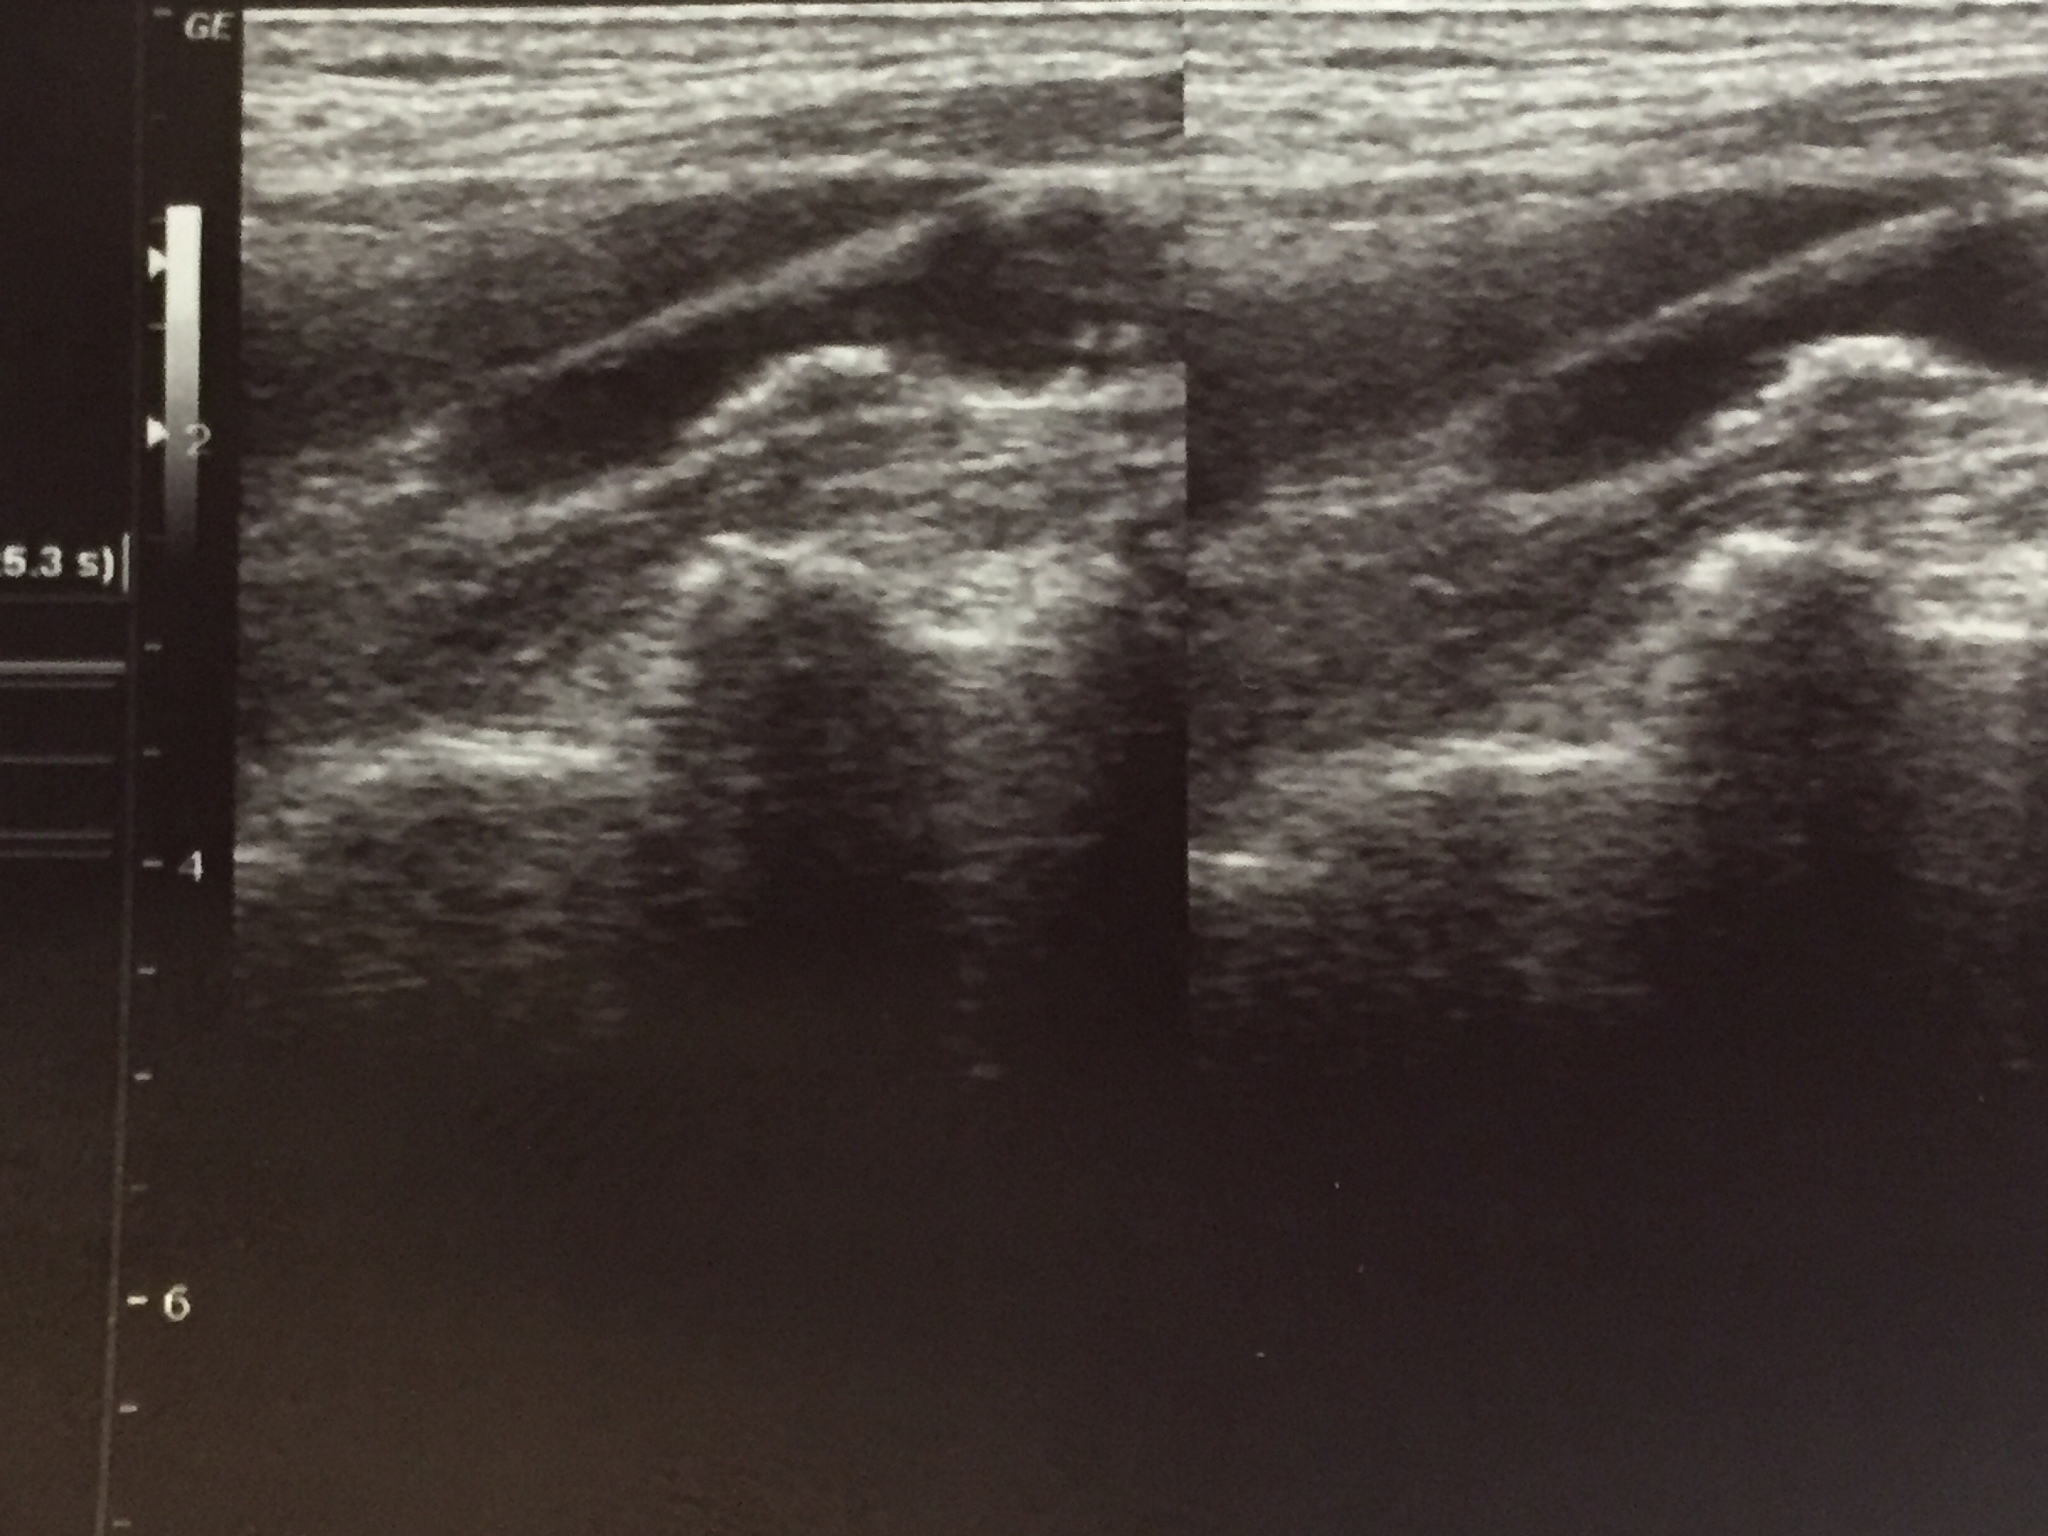

研究发现,颈动脉斑块的远端似乎与微弱的回声存在联系。此外,观察到斑块的远端运动与颈动脉的搏动轻微同步。

颈动脉搏动与斑块远端运动的潜在联系